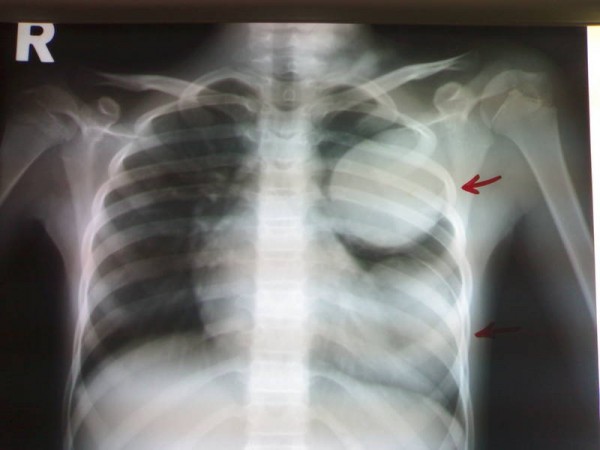

Парагонимоз — это паразитарное заболевание, вызываемое легочными сосальщиками, которое может вызывать серьезные проблемы со здоровьем. Люди, столкнувшиеся с этой болезнью, часто делятся своими переживаниями в интернете. Многие отмечают, что симптомы, такие как кашель, боль в груди и лихорадка, могут быть схожи с другими заболеваниями, что затрудняет диагностику. Некоторые пациенты рассказывают о том, как долго искали правильный диагноз, прежде чем врачи определили парагонимоз. В социальных сетях можно встретить фотографии, на которых изображены результаты анализов и рентгеновские снимки, что помогает другим людям лучше понять, с чем они могут столкнуться. Обсуждения также касаются методов лечения и реабилитации, где пациенты обмениваются опытом и советами. Важно, что такие разговоры помогают повысить осведомленность о заболевании и его последствиях.

- Рентгенологические исследования легких показывают затемнения в сегментах. Они имеют дугообразную форму. Видны паразиты и на рентгене черепа, если гельминты обосновались в мозге пациента.